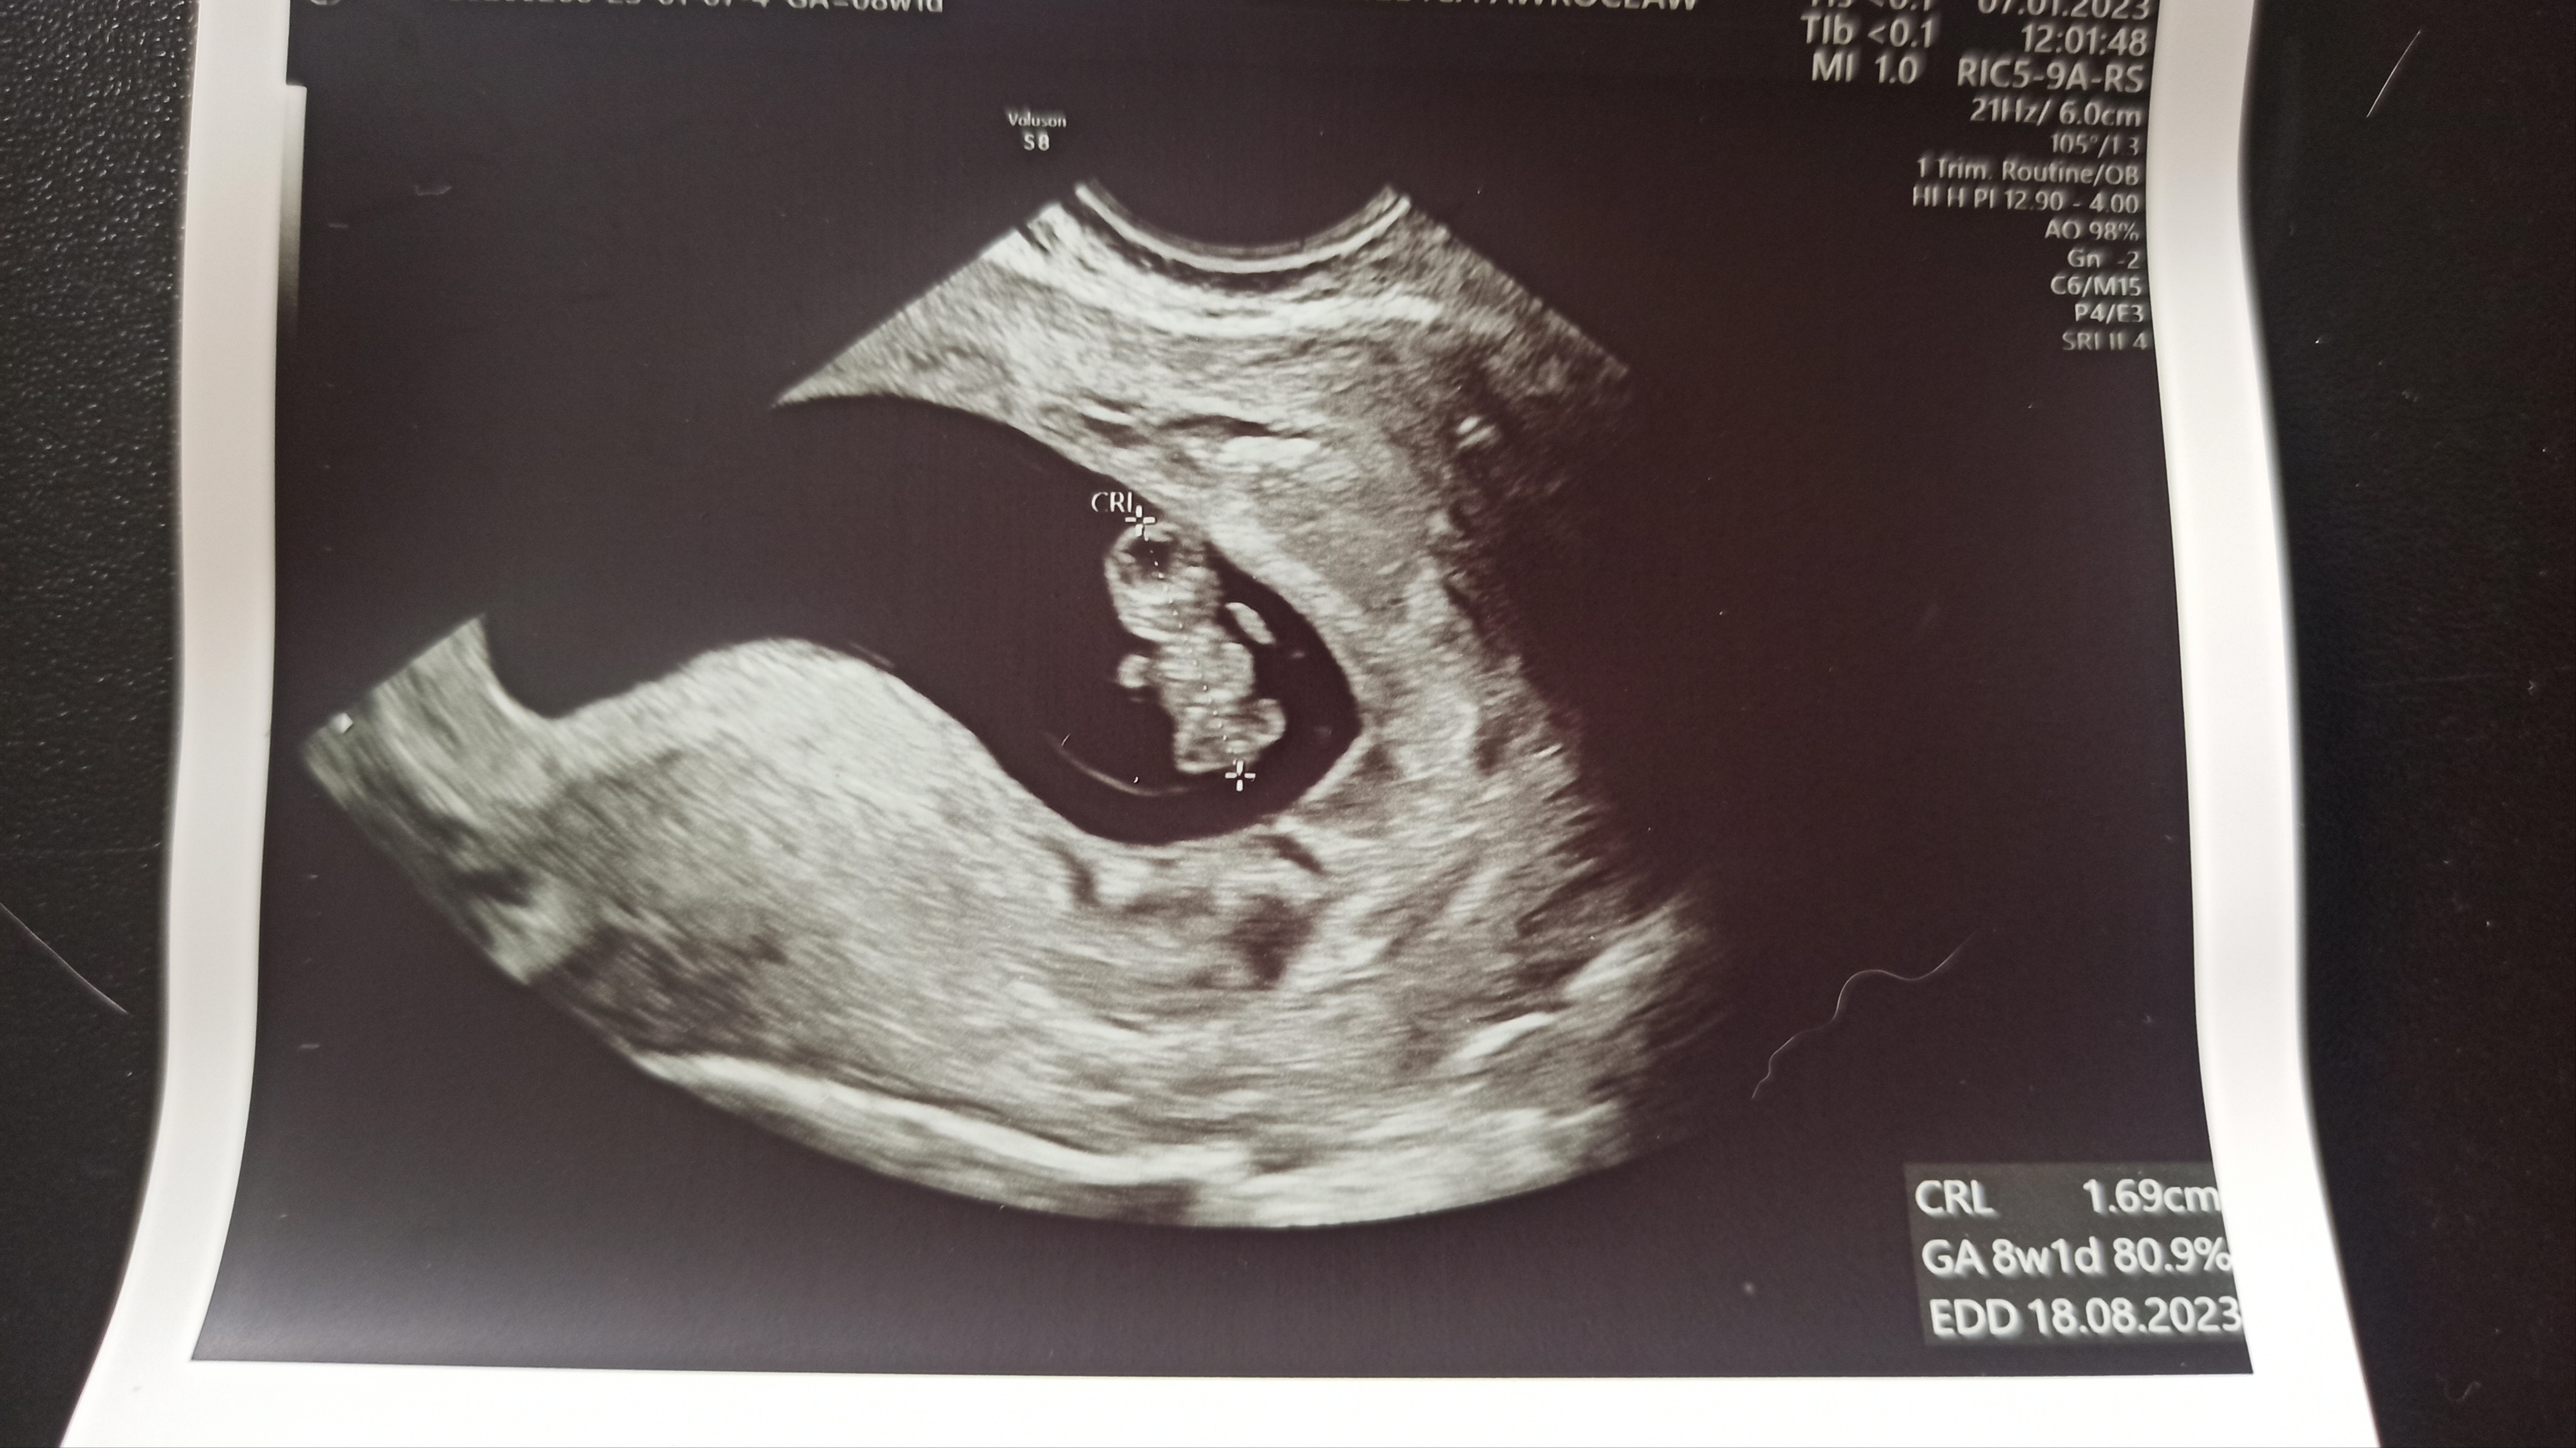

Już po wizycie, wszystko dobrze, mała dzidzi rośnie, jest teraz 8+1, mierzy 1.69cm. Karta ciąży zalozona, muszę się teraz na pappa umówić. A dziś mi strasznie niedobrze, ledwo doszłam do tej lekarki.

A tu jest jeszcze z innego kątaPiękniejszego małego człowieka jeszcze nie widziałam![]()